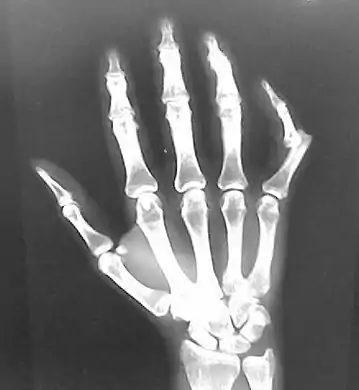

خلع في مفاصل مشط اليد .